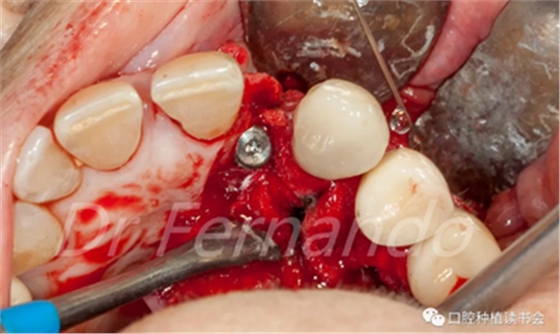

處理2分鐘后,用無菌的吸唾管吸除凝膠,用生理鹽水沖洗種植體表面10秒,然后用無菌吸唾管吸除剩余的鹽水溶液,取出敷料。下一步是用無菌敷料包住種植體,用透明質(zhì)酸鈉-哌拉西林-他唑巴坦溶液浸泡5分鐘后取出(圖14)。

圖14 使用抗生素溶液凈化種植體表面